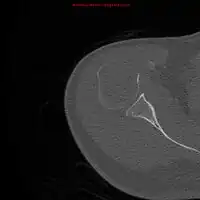

1.b. CT scan: solitary plasmacytoma upper arm near shoulder